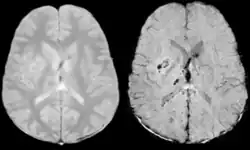

Vergleich einer axonalen Verletzung aufgenommen mit konventioneller GRE (links) und mit SWI (rechts) bei 1.5 T

Vergleich einer Hirnblutung aufgenommen mit konventioneller GRE (links) und mit SWI (rechts) bei 1.5 T